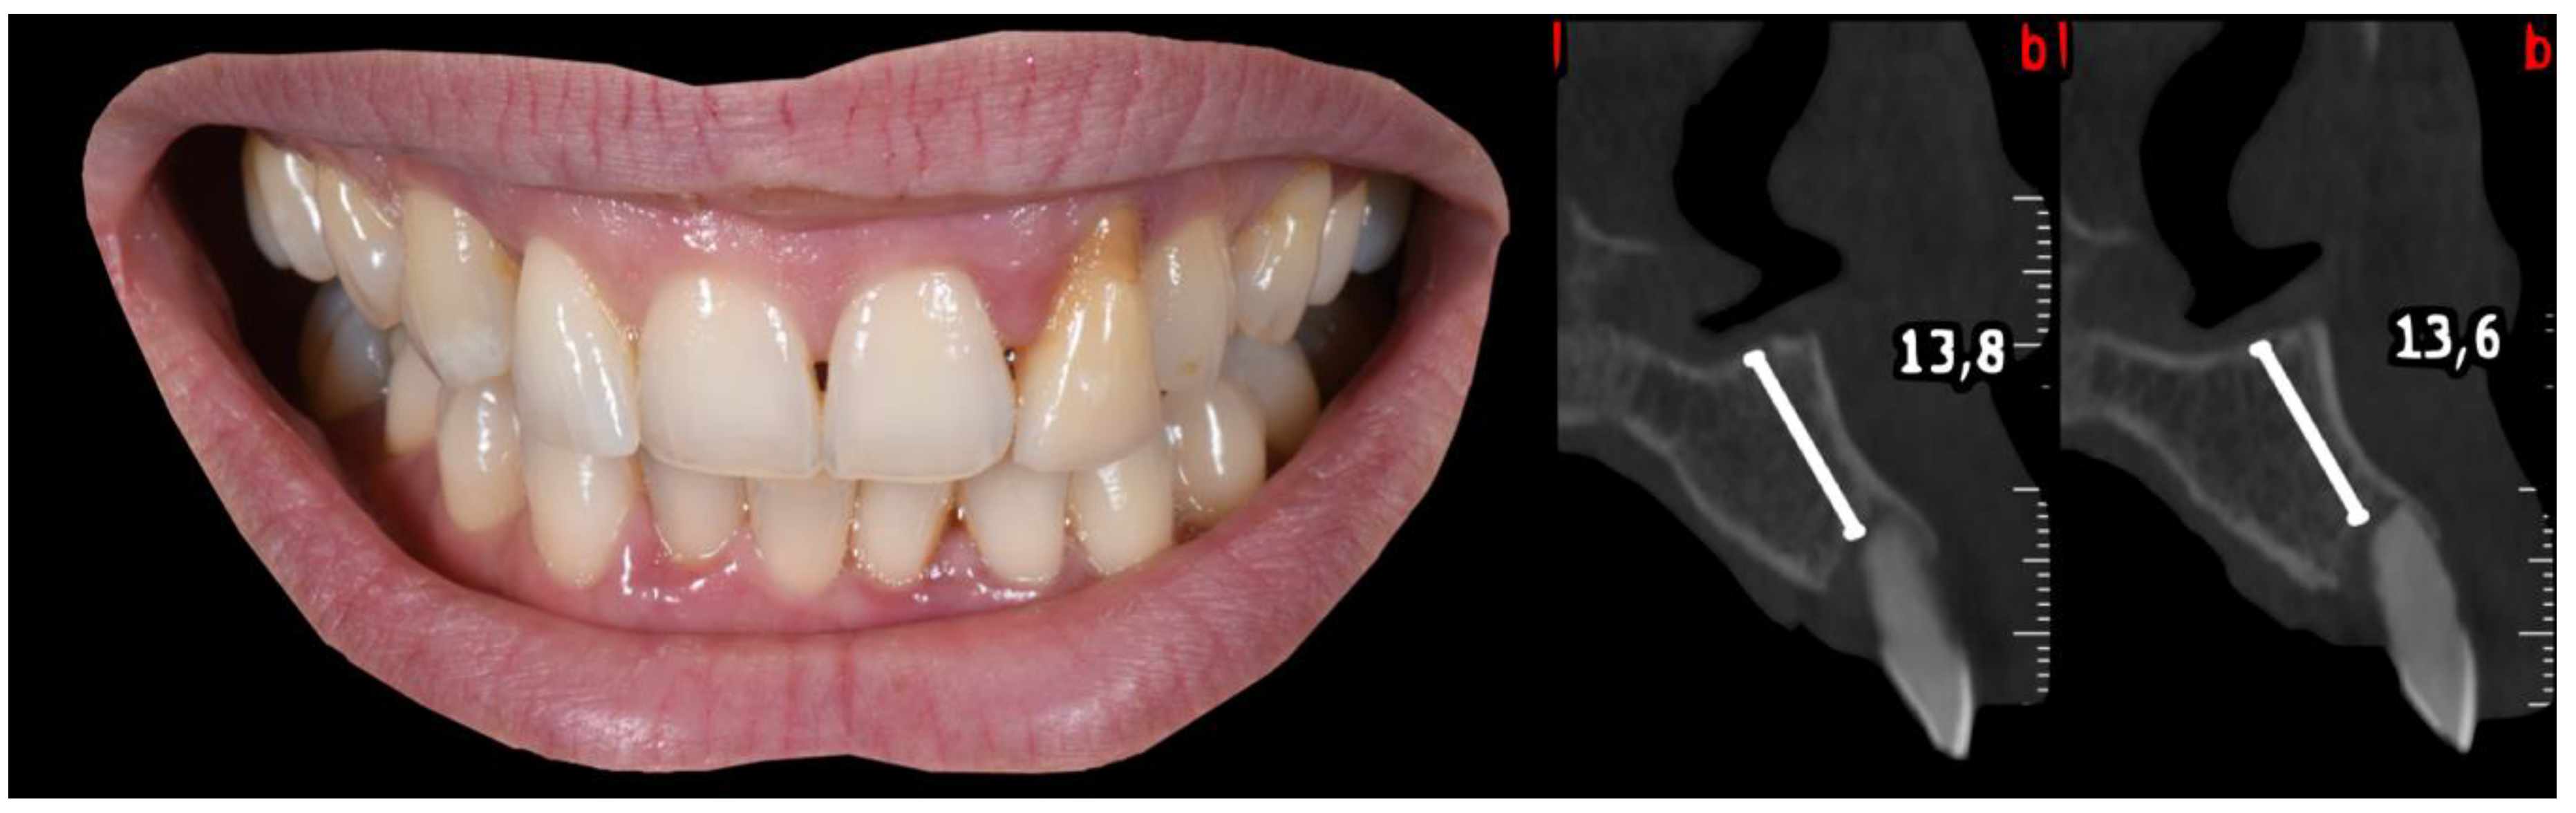

2. Case 1

2.1. “Report and Protocol”

2.2. Pre-Surgical Stage

3. Case 2